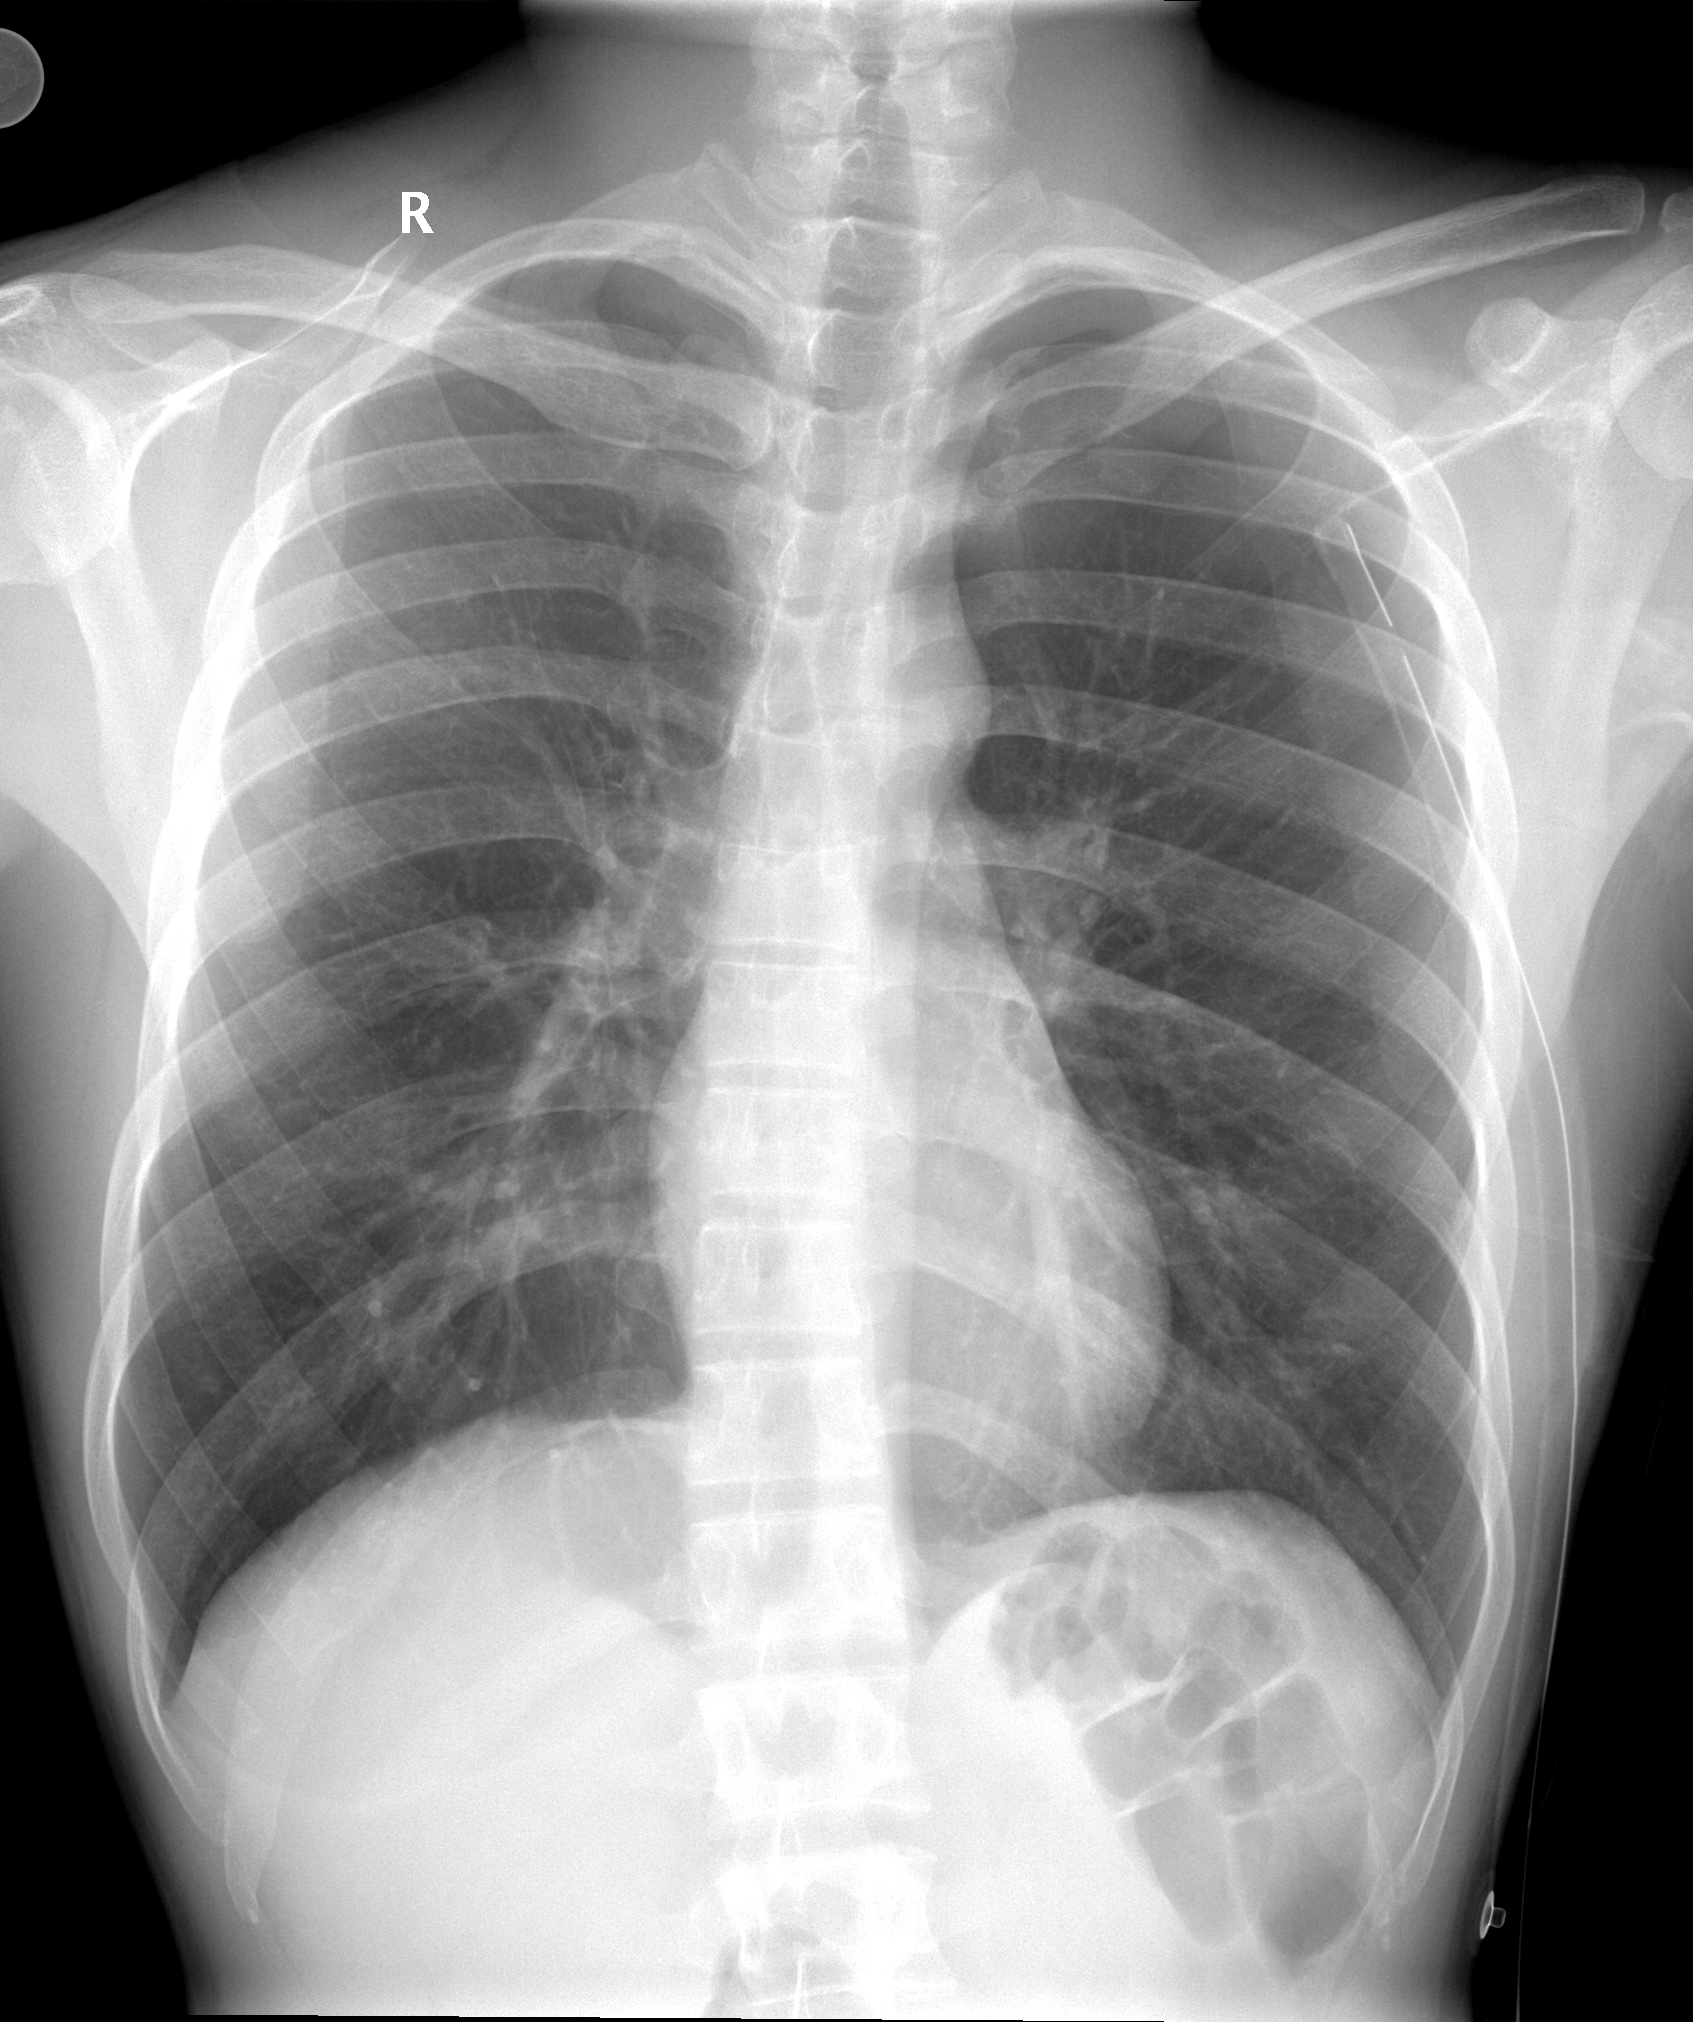

Рентгеновские снимки при врожденной эмфиземе легкого

Раздел: Визуальные уроки